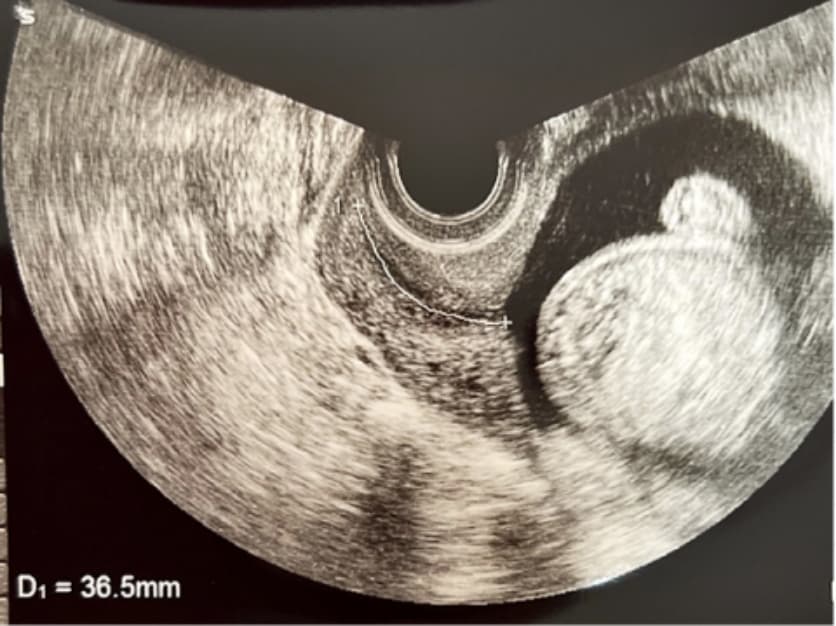

• 16週頃:内診エコーによる子宮頸管長計測、膣分泌物の異常細菌・クラミジア検査

内診エコーによる子宮頸管長計測写真

(流早産のチェック)

• 経膣エコーで子宮内の正常妊娠であるかを確認します。